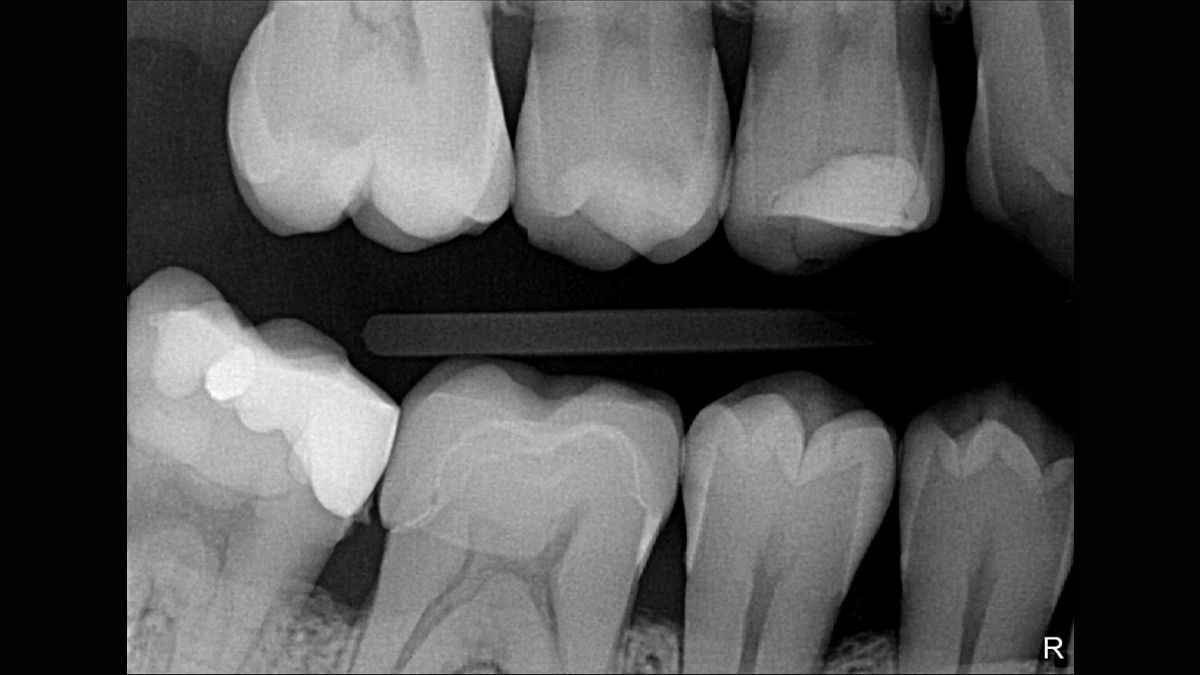

- Doskonała jakość obrazu – teoretyczna rozdzielczość 33 lp/mm (rozmiar piksela 15 μm)

Xios Supreme wyposażony jest w suwak dynamicznego wyostrzania obrazu, co umożliwia dostosowanie ustawień diagnostycznych pod kątem ostrości. Dostępne są również suwaki do modyfikacji jasności oraz kontrastu fotografii. Ustawienia te pozwalają na dostosowanie obrazu odpowiednio do potrzeb prowadzonego leczenia, zwiększając możliwości diagnostyczne oraz usprawniając pracę w gabinecie.

Czujnik posiada funkcję filtrowania z pięcioma dostępnymi opcjami: stomatologia ogólna, endodoncja, periodontologia, odbudowa oraz higiena, które pozwalają na dopasowanie widoku do konkretnej sytuacji klinicznej.

Diagnostyka wewnątrzustna za pomocą obrazowania rentgenowskiego przeprowadzana techniką kąta prostego jest obecnie standardem. Aby ją wykonać niezbędny jest pozycjoner, wspierający odpowiednie wyrównanie czujnika pod prawidłowym kątem.